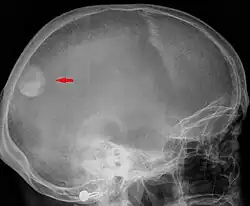

Zdjęcie boczne czaszki – widoczny oponiak